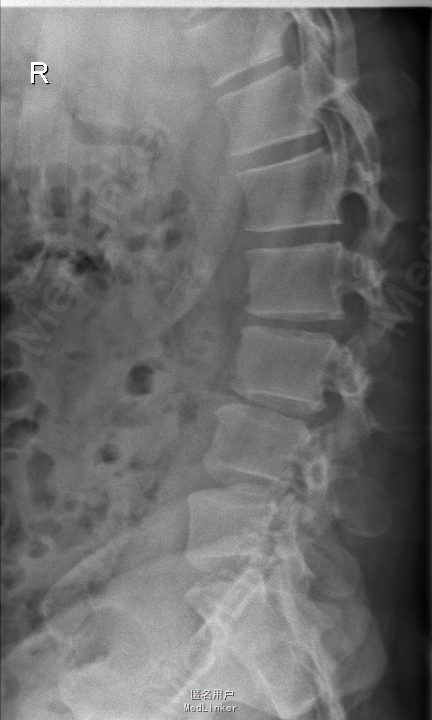

查体:腰部叩痛,腰部活动受限,左侧膝内侧、小腿外侧、内踝、足部感觉减退,右侧小腿、足背感觉减退,屈髋、伸膝、踝背伸肌肌力左侧4级,右侧4-5级,踇背伸、跖屈肌肌力左侧3-4级,右侧4级,双侧膝腱反射+,跟腱反射+,双侧巴氏征阴性,直腿抬高试验左侧40°阳性,右侧阴性。 辅助检查: X-ray:腰椎退行性变,多节段不稳 CT:腰椎间盘突出并椎管狭窄伴钙化,腰2-3,3-4,4-5,腰5骶1 MR:腰椎间盘突出并椎管狭窄,腰2-3,3-4,4-5,腰5骶1 上传受限无法全部上传,见谅

诊断:腰椎间盘突出症并椎管狭窄 处理:1、完善相关辅助检查,明确诊断,有无手术指证; 2、完善手术评估,有无手术禁忌,手术风险及并发症; 3、在全麻下行腰椎后路多节段减压椎间植骨融合内固定术 4、腰2-3,腰3-4行开窗减压,腰4-5,腰5-骶1行椎间Cage植骨融合

随访:1、应常规术后1个月、3个月、半年随访; 2、术后患者腰痛较前减轻,下肢麻木感觉较前好转,下肢活动较前有力,屈髋、伸膝、踝背伸肌肌力左侧4级,右侧4-5级,踇背伸、跖屈肌力左侧4级+,右侧4-5级,左侧肢体抬高试验阴性。 讨论:1、多节段腰椎间盘突出,手术指证把握 2、责任节段的确立,以影像学间盘突出节段为依据,还是联系临床表现? 3、手术节段的确立,以影像学与临床表现确立责任节段间盘为依据,还是术中探查为金标准? 4、多节段间盘突出,开窗髓核VS椎间植骨融合? 5、开窗髓核与椎间植骨融合相结合,如何确定融合节段与开窗节段? 6、多节段内固定,腰椎活动度影响,稳定与腰椎活动功能的平衡?